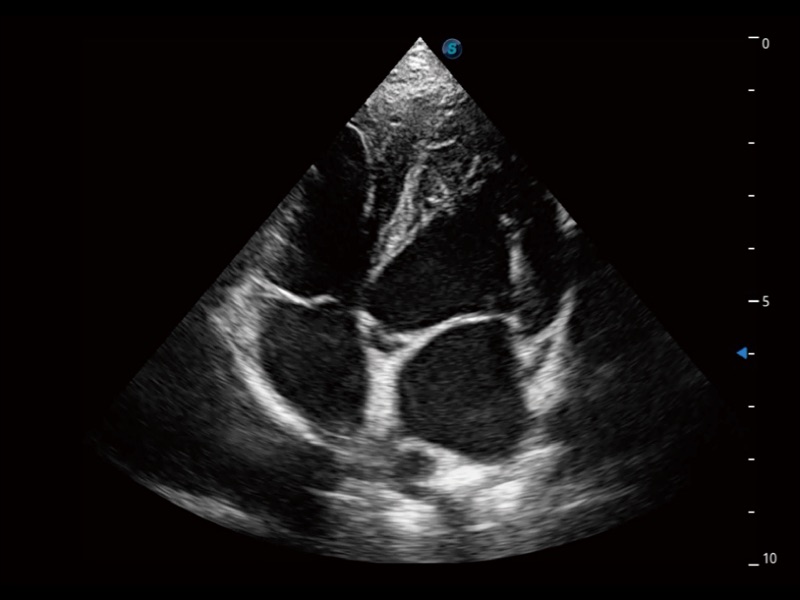

能夠基于左心室壁追蹤和辛普森法,自動(dòng)計(jì)算射血分?jǐn)?shù),支持多個(gè)可移動(dòng)點(diǎn)描跡,與手動(dòng)測(cè)量相比,極大節(jié)省了動(dòng)物醫(yī)生的時(shí)間和精力。

通過(guò)360度任意調(diào)節(jié)3條M型取樣線,在同一心動(dòng)周期上觀察心臟不同位置的運(yùn)動(dòng)曲線,得到準(zhǔn)確的心功能測(cè)量數(shù)據(jù),有效評(píng)估心肌運(yùn)動(dòng)及左心室功能。